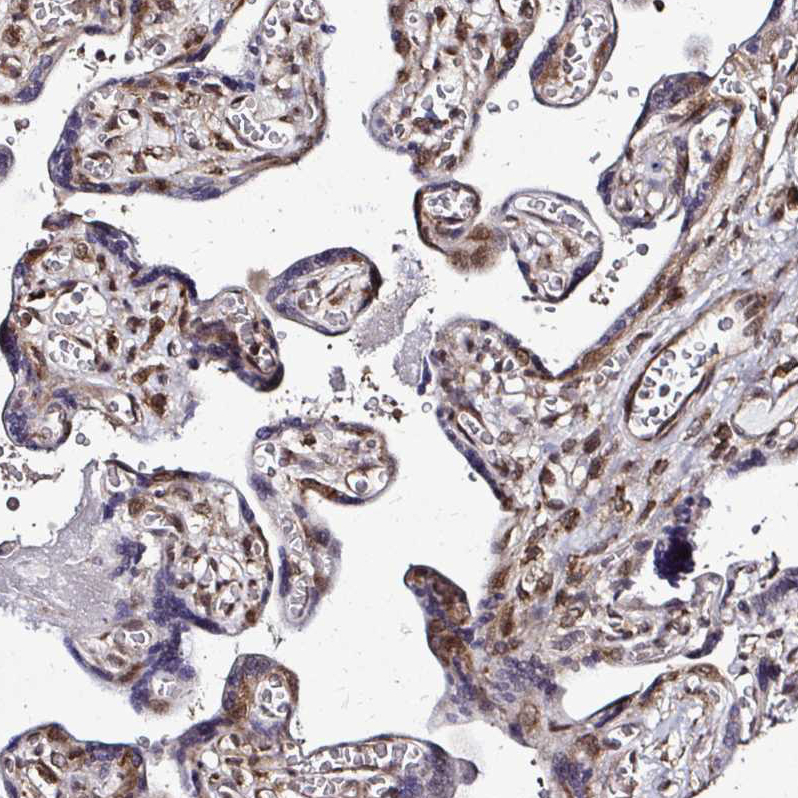

Immunohistochemical staining of human fallopian tube, liver, placenta and testis using Anti-FMR1 antibody HPA056084 (A) shows similar protein distribution across tissues to independent antibody HPA050118 (B).